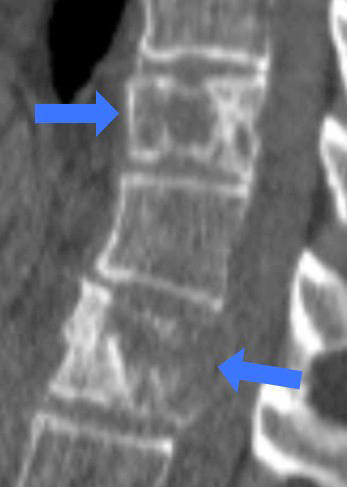

整形外科医今泉佳宣氏人間の骨は約200個あります。どの骨も骨折する可能性があり、その治療は決して易しいものではありません。まず正確に診断することが大切です。骨折の診断には単純X線写真を用いますが...